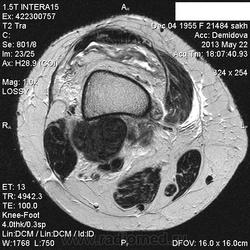

Вчера пациентка на рентгенографию коленного сустава приходила, нашла у нее изменения метадиафиза бедренной кости ( снимки затра выложу-не успеваю) , порекомендовала МРТ.Сегодня она у меня же и проходила исследование. ЗНО однозначно?Либо виллонодулярный синовит? Но разрушение кортикала ? за счет масс-эффекта? не пойму...

Сейчас вообще не пойму-образование , похоже, не из кости растет, а вызывает атрофию ее.Или мне кажется?

Остановилась на пигментном виллонодулярном синовите.

Никогда не видел сам вилонодулярного синовита, но мне кажется Вы правы, по сигнальным харатеристикам на него больше всего похожи изменения. И в большеберцовой кости изменения такие же.

С учетом тотальности поражения сустава по DICOM - без вариантов пигментный...